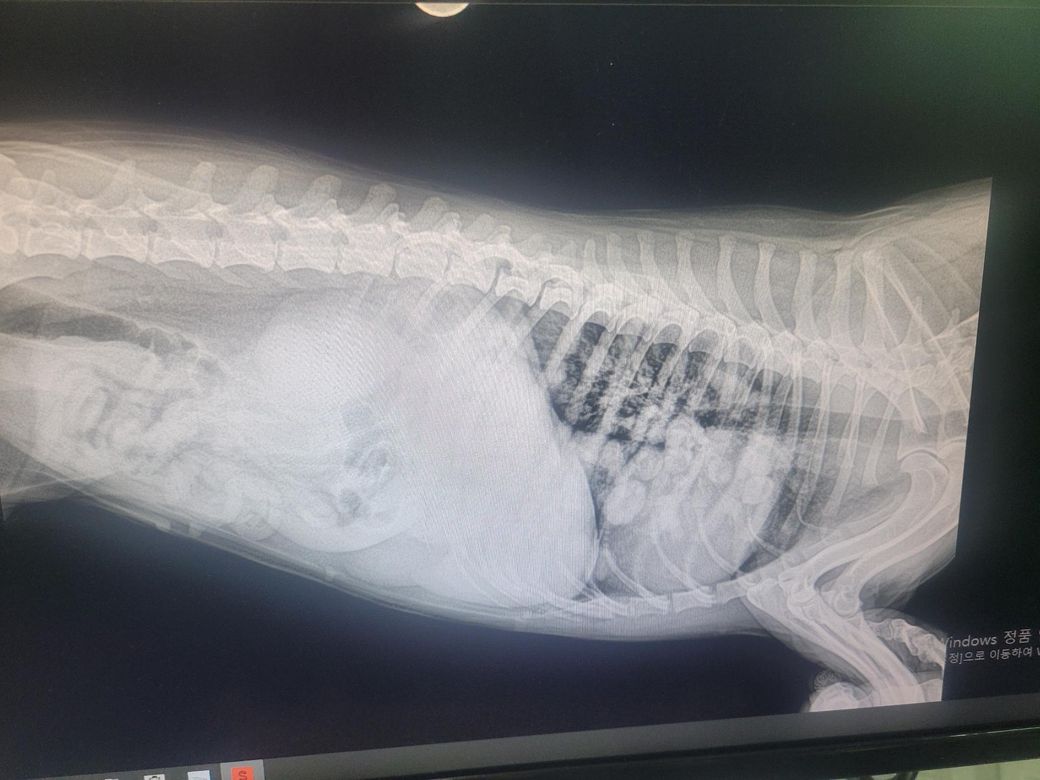

강아지 엑스레이 사진봐주실수있나요?

엑스레이 사진에선 종양이 여러개라는데..이런경우 씨티촬영 하게되면 종양이 1개인 확률이 생길수도 있나요?씨티 찍으려니..마취를 해야되서 어떤방식으로 강아지를 치료하고 해야될지 막막합니다

이전에 원발성보다는, 전이성 폐종양이 의심되는 상황으로 말씀드리긴했습니다만, 다만 단순 방사선만으로는 해당 병변이 원발성인지 혹은 전이성인지, 전이성인 경우 어디로부터 전이된 종양인지는 명확한 판단이 어렵습니다. 일반적인 상황들에 준해서 말씀드린 거긴 합니다만, 형태로만 보아서는 전이성의 가능성이 더 높은게 사실입니다.

걱정하시는 부분은 이해하겠으나, CT는 종양의 진단, 수술 가능성 평가, 전이 여부 판단에 있어 가장 정확한 검사입니다. 다만 현재 상황에서 엑스레이만으로는 종양의 성격(암인지, 염증인지, 원발성인지, 전이성인지)이 의심이 될 뿐, 명확히 구별할 수 없고, CT 후 필요 시 조직검사로 확진해야 치료 방향이 정해집니다. 전이성 폐종양일 경우 수술은 제한적이지만, 단일 병변이면 외과적 절제, 다발성 병변이면 항암 또는 완화요법을 고려할 수 있습니다. 다만, 노령견인 경우 CT를 위한 마취에 제한이 생길 수 있어서 이 부분은 내원 후 수의사 상담이 필요합니다. 마취 위험도 및 방사선 양상 등을 종합하여 치료 방향 고려해주실 겁니다.

그럴 가능성은 0에 가까워 보입니다. 앞으로 어떻게 치료해야 할지는 CT 결과를 보고 판단해야 하는 것들이니 주치의와 상의 후 촬영 진행하시기 바랍니다. 막막해하기만 하다가 시간만 흐르면 더 빨리 죽을 뿐입니다.